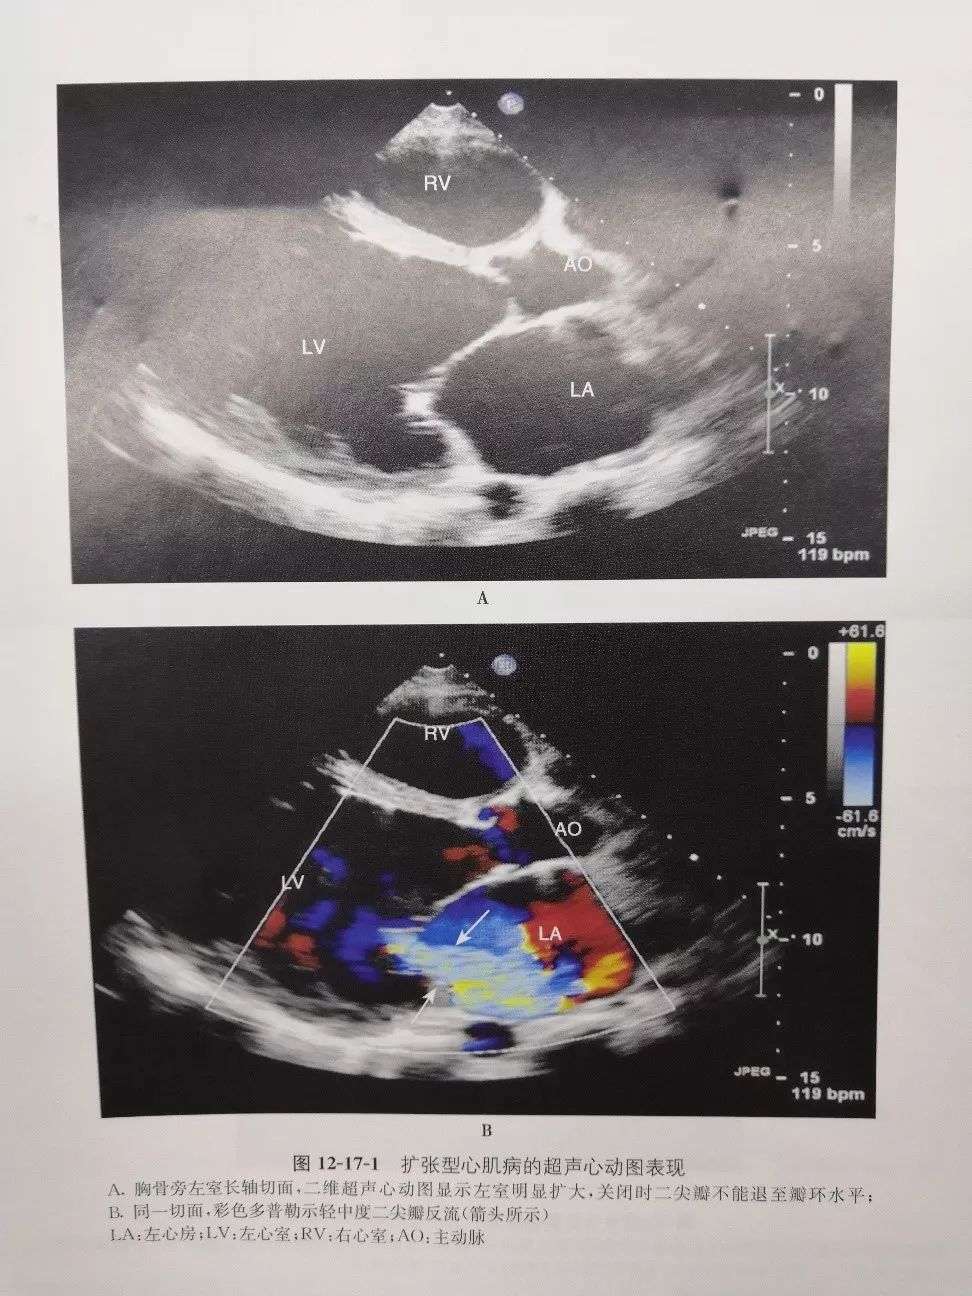

除此之外,体检发现“心影扩大”就要去心血管内科详细检查了。“拍胸片(X线检查)和查心电图是必须要做的检查”,说到这里,彭教授提醒广大基层医生:有了可能患扩心病的线索后,心脏彩超检查基本可以确定扩心病诊断。

(图注:扩心病超声心动图[2])

“扩心病具有多种原因,只要心脏扩大+心脏收缩功能下降就可以考虑扩心病诊断,但真正扩心病需要排除其他已知原因后才能诊断。典型的扩心病多有家族史,由基因突变所致,可考虑做基因检测,提早干预和治疗,也利于优生优育。”彭教授补充道。